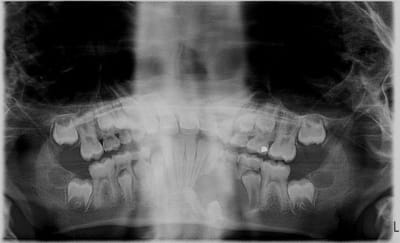

pano comme on a pu

a piori je pense enlever la 74 et compter sur l'élimination spontanée du kyste

pas de chance,c'est au niveau de 74 qu'on ne voit pas gd chose: une petite rx?

cela dit vu l'evolution de 44,mme si léger décalage par comparaison, cela ne doit pas poser de pb

autant pr moi j'ai regardé la 75

la pano n'est vraiment pas terrible,mme le kyste je ne le discerne pas tant(mais où st donc mes lunettes)

par contre tout en bas ,les 2 images,sont les germes de 33 et 34,j'imagine

franchement je ne vois pas gd chose sur ta pano